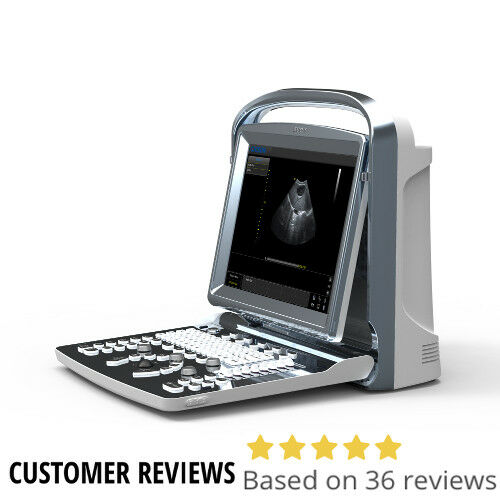

DIAGNOSTIC ULTRASOUND MACHINES FOR SALE

Chison eBit 60 Color Doppler Ultrasound Scanner CW w/ Cardiac and Linear Probes

Sale price$ 13,365.42

Regular price$ 16,299.30